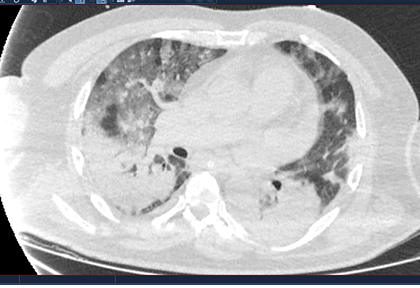

Routine clinical laboratory assays were performed in the hospital’s clinical laboratories. Clinical and laboratory information was extracted from the patients’ medical records. C reactive protein (CRP) in plasma was measured by immunoturbidimetry (Beckman Coulter, Krefeld, Germany). Interleukin-6 (IL-6) levels in plasma were measured by electrochemiluminescence (Siemens Medical Solutions Diagnostics, Siemens Healthcare, Erlangen, Germany). CT scans were read by experienced radiologists who scored results by severity using the criteria shown in Figure 1.

Figure 1. Clinical assessment of pneumonia severity based on computed tomography (CT) scores.

Scoring method: Mild (CT-1)—no more than three ground-glass opacities of <3 cm maximum diameter. Moderate (CT-2)—more than three ground-glass opacities; less than 50% involvement by visual assessment. Medium-heavy (CT-3)—ground-glass opacities and pulmonary consolidation; 50-70% involvement by visual assessment. Severe (CT-4)—diffuse ground-glass opacities with or without consolidation; more than 75% involvement by visual assessment.